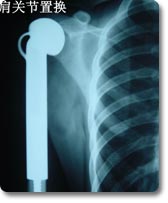

四肢大关节人工关节置换术

关节置换可以说是本世纪骨科手术最伟大的突破之一。目前它已应用於治疗肩关节、肘关节.腕关节、指间关节 、髋关节、膝关节及踝关节等疾患,但以全人工髋关节及膝关节置换最为普遍。对骨关节炎、股骨头无菌性坏死、老年性股骨颈骨折等疾病具有明显治疗效果,我科目前已开展各种置换手术800余例,疗效受到患者普遍肯定。